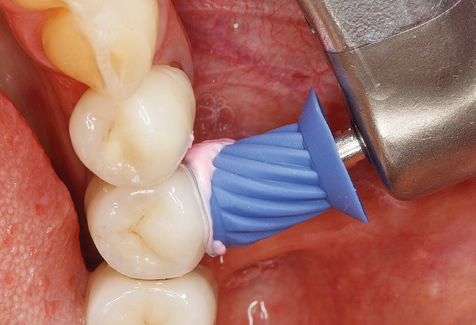

Good illumination of the working field facilitates the process considerably. The system used by the authors achieves this thanks to a 5x LED ring integrated in the handpiece. Naturally, a range of working tips for different indications is also offered. A straight, universally employable tip is the basic instrument required for machine cleaning of natural teeth (Fig. 5a and b). Curved tips, which allow access to exposed furcations, are also available for hard-to-reach areas in the posterior region (Fig. 6).

Of course, working tips for the cleaning of implant surfaces are also indispensable for SPT in patients fitted with implants. The implant cleaning attachment on the system used here is characterised by its tapered, hexagonal design. This design allows light, atraumatic penetration of the peri-implant pocket and displays a good cleaning performance (Fig. 7).

Fig. 4: Flexible probes with millimetre markings are recommended for the probing of dental implants (e.g. Colorvue Kit PCV11KIT6, Hu­Friedy). – Fig. 5a and b: A straight working tip (1P, W&H Dentalwerk Bürmoos GmbH) is a suitable instrument for use on all natural teeth. – Fig. 6: Curved working tips (3Pr/3Pl, W&H Dentalwerk Bürmoos GmbH) lend themselves to the processing of difficult-to-reach areas of the tooth and root surfaces (e.g. furcations). – Fig. 7: The tapered, hexagonal implant cleaning tip (1I, W&H Dentalwerk Bürmoos GmbH) permits atraumatic and efficient cleaning of the crown and abutment surfaces. – Fig. 8: Titanium and carbon curettes are suitable instruments for the manual cleaning of the implant surfaces.